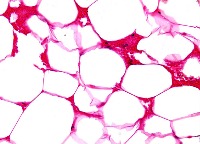

Adipose Tissue

Lipoma

Skeletal Muscle